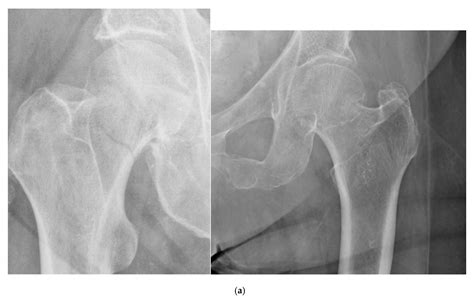

A non displaced fracture occurs when a bone breaks but the bone fragments remain in their original position. This type of fracture is often less severe than displaced fractures, where the bone fragments are misaligned. Non displaced fractures can occur in any bone in the body, but they are most commonly seen in the wrist, ankle, and spine. These fractures are typically the result of minor trauma, such as a fall or a direct blow to the bone.

• Osteoporosis: This condition weakens the bones, making them more susceptible to fractures. Even minor injuries can result in a non displaced fracture in individuals with osteoporosis.

• Imaging Studies: X-rays are the most common imaging tool used to diagnose non displaced fractures. They can provide a clear view of the bone and help determine the location and extent of the fracture. In some cases, additional imaging studies such as CT scans or MRI may be necessary to get a more detailed view of the injury.

Individuals with osteoporosis are at a higher risk of fractures due to weakened bones. Non displaced fractures in individuals with osteoporosis may require special considerations, including:

• Bone Health: Individuals with osteoporosis should focus on maintaining bone health through a balanced diet, regular exercise, and appropriate supplementation. This can help reduce the risk of fractures and promote faster healing.